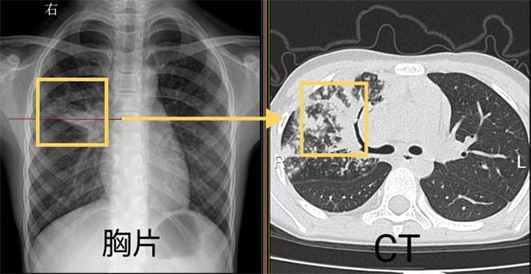

我們先通過同一個病人的胸片和胸部CT對比看一下吧。

胸片黃框區(qū)域顯示沒有異常,同一位置CT顯示少許肺炎病灶。

對比我們可以發(fā)現(xiàn),胸片可以提供初步的診斷依據(jù),胸部CT能更清晰的顯示病灶形態(tài)及一些微小病灶,比如實變、空洞、支氣管壁的增厚等。因此,在小兒肺炎支原體肺炎的診斷中,胸部CT具有一定的優(yōu)勢。